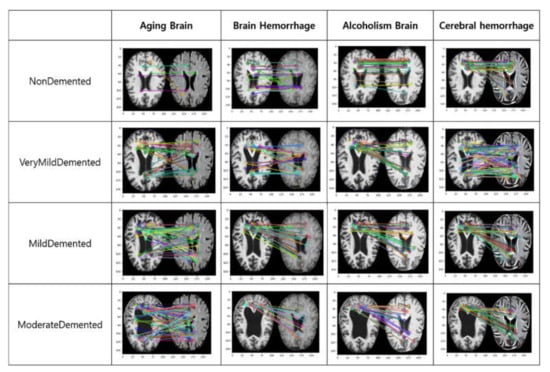

A second assessment compares the style-transferred image with similar features to the dementia stage. It uses a feature-matching algorithm. The feature-matching algorithm extracts various features from the image and has the advantage of being able to extract features even if the image is rotated, enlarged, or reduced. It is judged to be a similar image as more extracted features appear []. It is possible to determine which part of the style transmitted image is similar to the dementia image. Figure 9 shows the result of comparing the characteristics of the style transmitted image with the dementia stage.

Figure 9.

The result of comparing the characteristics of the style transmitted image with the dementia stage.

As a result of comparing the features in Figure 9, the most common features of the aged brain were extracted in all dementia stages. In addition, in the case of cerebral hemorrhage, very weak dementia and mild dementia showed similar characteristics, and, in the case of alcohol brain and traumatic brain, many similar characteristics were extracted, not only in all dementia stages, but also in the brain without dementia.